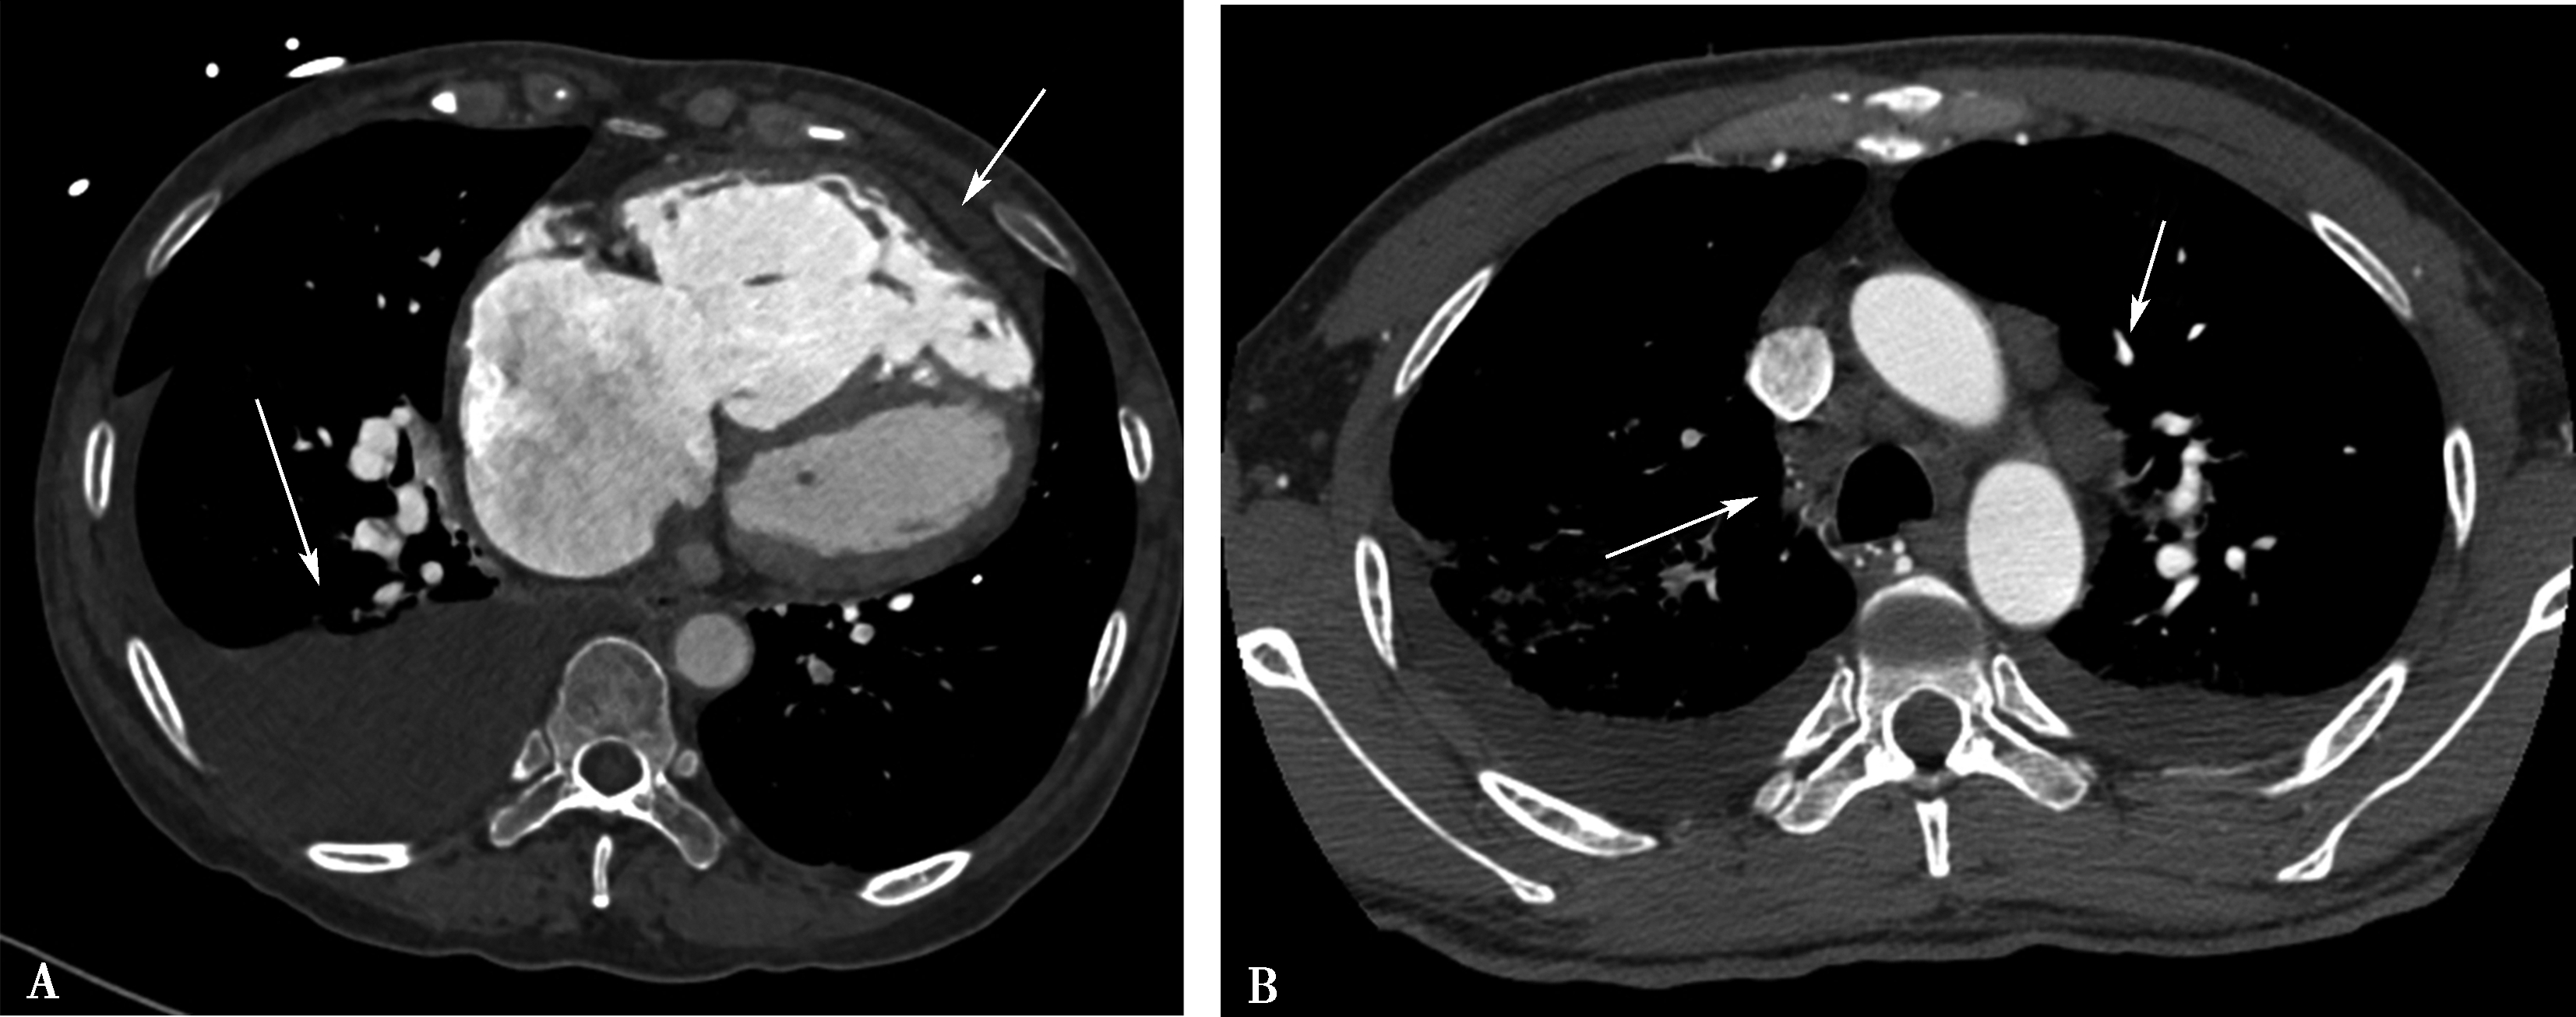

(二)双期扫描法(图8-1-5)

1.患者仰卧位,足先进,仰卧于检查床上。对检查范围以外的部位用铅衣、铅帽遮盖做好防护。

2.对比剂 对比剂浓度370mgI/ml,采用单筒高压注射器团注,流率为4.0~5.0ml/s,对比剂总量为70~90ml,如加做下肢静脉造影,可增加对比剂剂量为120~150ml。

3.扫描的范围 从肺尖到膈肌。

4.扫描采用的对比剂跟踪技术,监测层面设定在上腔静脉入右心房的层面,ROI定为上腔静脉,触发阈值定义为80~100HU。

5.当ROI的CT值达到阈值时启动增强扫描程序。实行双期扫描,第一期为肺动脉期,从肺尖扫描至膈肌,第二期为主动脉期,由膈肌扫描至肺尖,双期扫描范围一致。双期扫描的意义在于:①充分保证了对比剂团注时间与肺动脉CT数据采集时间的吻合;②肺动脉高压或/和右心功能不全循环时延长者,是一弥补措施;③多期观察可以辨别对比剂充盈不均造成的假象;④有利于对肺灌注的评价;⑤主动脉期可以兼顾观察左心系统的病变。

图8-1-3 对比剂智能自动跟踪触发技术

造影剂智能自动跟踪触发技术能够准确获得扫描启动时间点并及时启动扫描

图8-1-4 常规肺动脉CT造影横断图及重建图像

图8-1-5 CTPA两期扫描应用:患者,男,37岁,二尖瓣狭窄,肺循环高压,怀疑肺栓塞。第一期右肺下叶基底段对比剂充盈不充分(ABC↑);第二期充盈充分(DEF↑),排除肺栓塞诊断